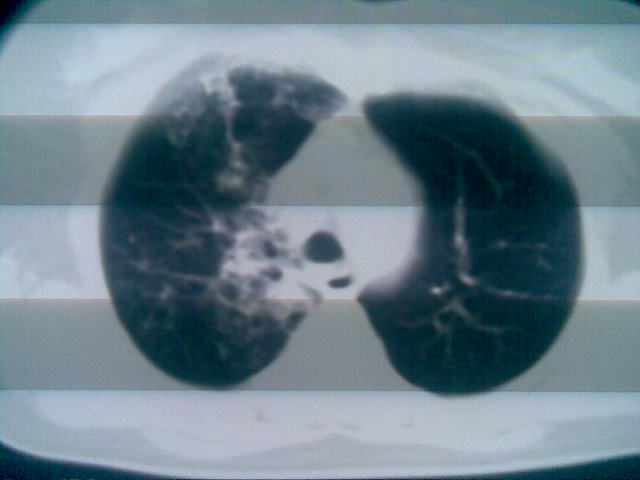

两上肺均见有斑片条结及蜂窝状环状低密度影,以右侧居多,考虑肺结核并支扩可能。

以下是引用sunbin在2010-1-6 15:51:00的发言:[br]两上肺均见有斑片条结及蜂窝状环状低密度影,以右侧居多,考虑肺结核并支扩可能。

支持!貌似上肺单纯支扩少见。